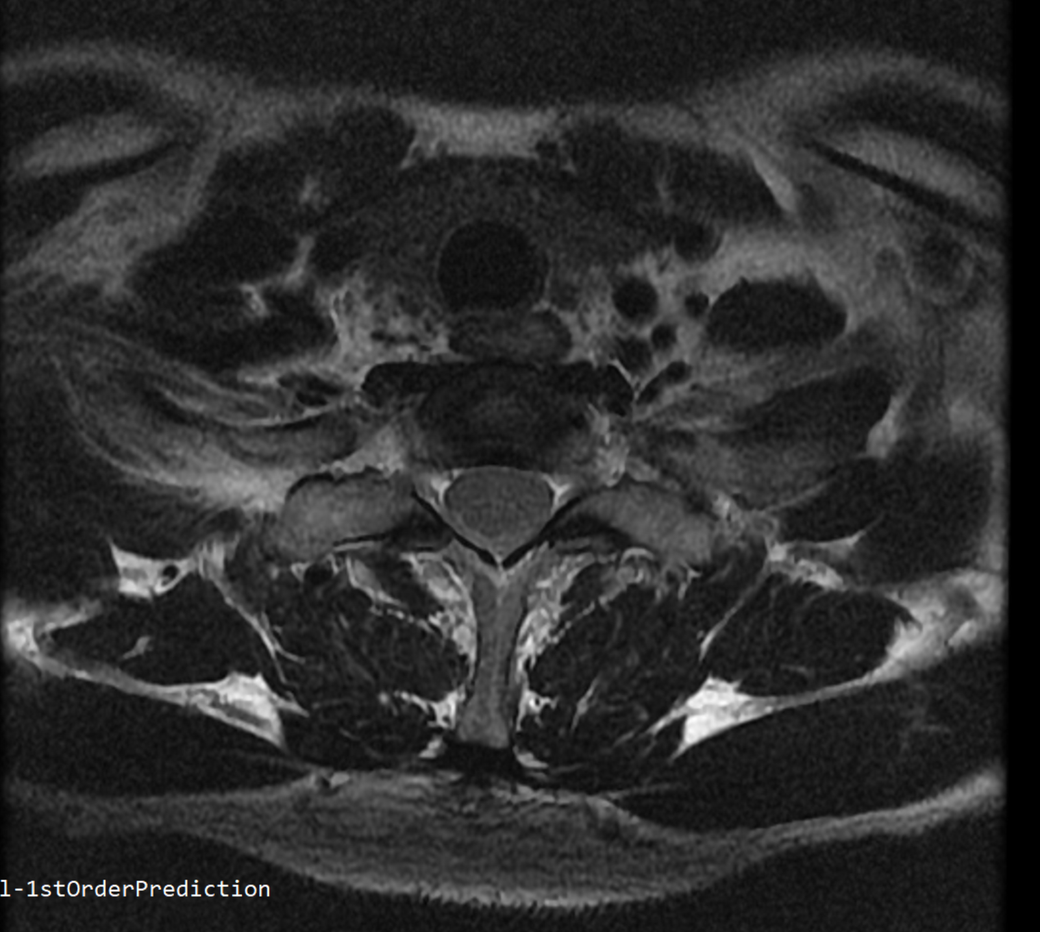

안녕하세요 목 경추 상단부터 순서대로 mri 촬영인데요

전체적으로 봐주시면 감사하겠습니다

하단8번 신경쪽도 나오는건지.. 봐주시면 감사하겠습니다

• 3번 째 사진